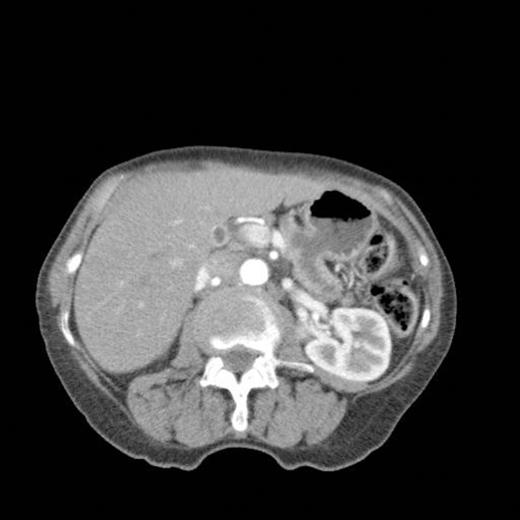

A subsequent CT scan done a year later confirmed the persistence of the gastro pancreatic fistula with polypoid herniation into the stomach and this was thought to represent main duct IPMN with mucinous tumour herniation into stomach (Fig 4). An upper GI endoscopy confirmed the gastric opening of the fistula at 50 cm on the lesser curve with a mucus plug sealing the opening (Fig 5). Biopsies were taken from around the fistulous opening and this was reported as non-specific inflammation. Again, a surgical option was offered that was declined by the patient and hence it was decided to continue with regular follow up and conservative management.